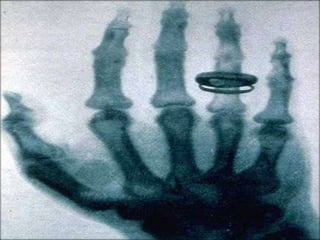

ANTECEDENTES DESCUBRIMIENTO DE LOSRAYOS “X”. el 8 de noviembre de 1895 se descubren los rayos x; el físico Wilhem Conrad Röntgen , realiza experimentos con los tubos de Hittorff-Crookes (o simplemente tubo de Crookes).